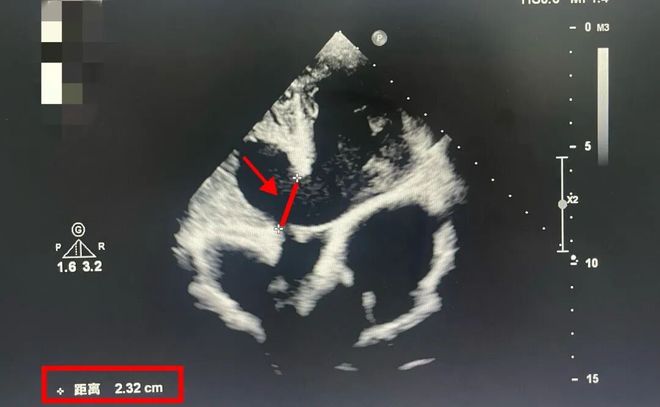

彼时,14岁的李小并不知道,他的心脏缺口已经“裂”开长达22毫米。

什么概念?室间隔缺口>5毫米,就一定要动手术“维修”了。

而李小心脏的这个裂口,已经超过正常手术指征的4倍。他的心脏射血分数已经低于50%(正常是50%-70%)。

这意味着,李小心脏的泵血战斗力,一直在走“下坡路”。再拖下去,就是心衰。能活到几岁?没人敢讲。

红色线段标注出来的那一小截,就是李小的室间隔缺损缺口